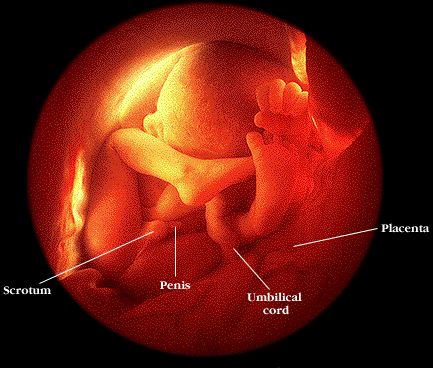

baby girl at 5 months  baby boy at 8 months